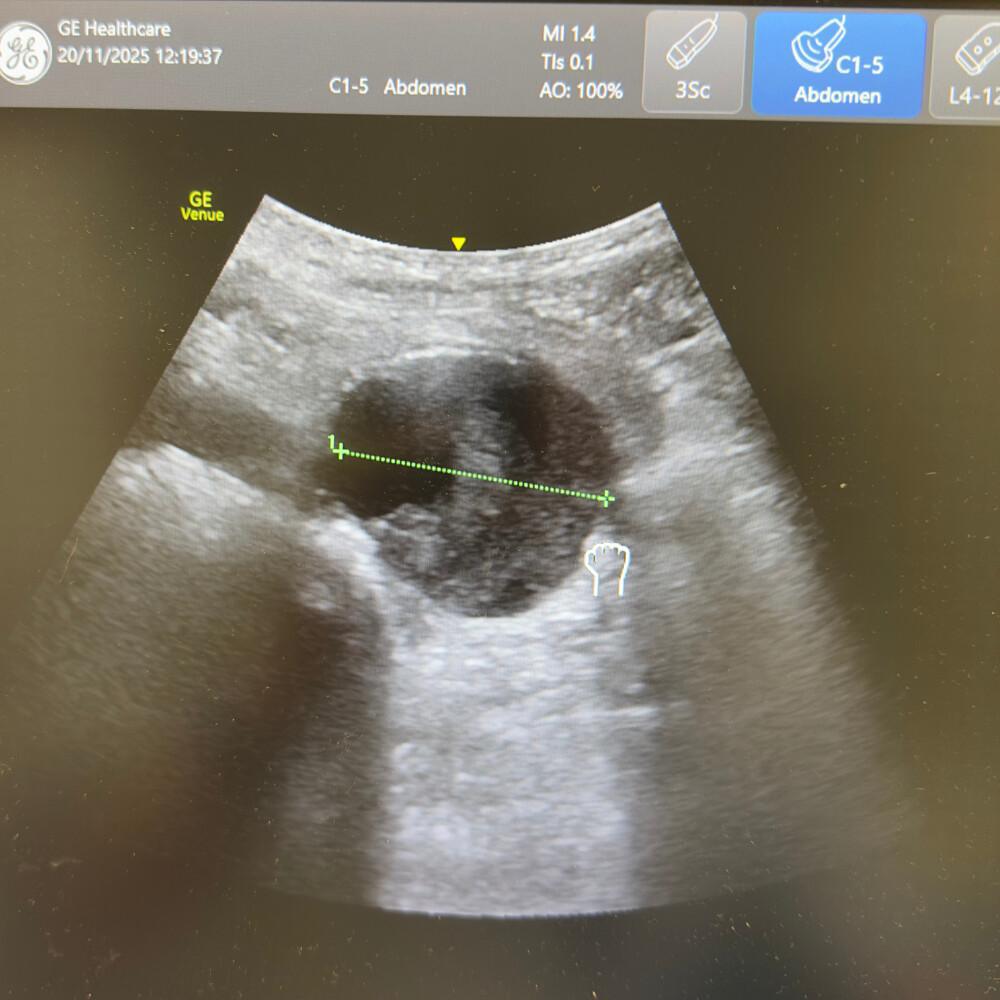

Le diamètre externe-externe doit être mesuré perpendiculairement au faisceau, sans compression.

- Diamètre normal : < 3 cm.

- Anévrysme fusiforme ou sacculaire : dilatation > 3 cm, souvent avec calcifications pariétales.